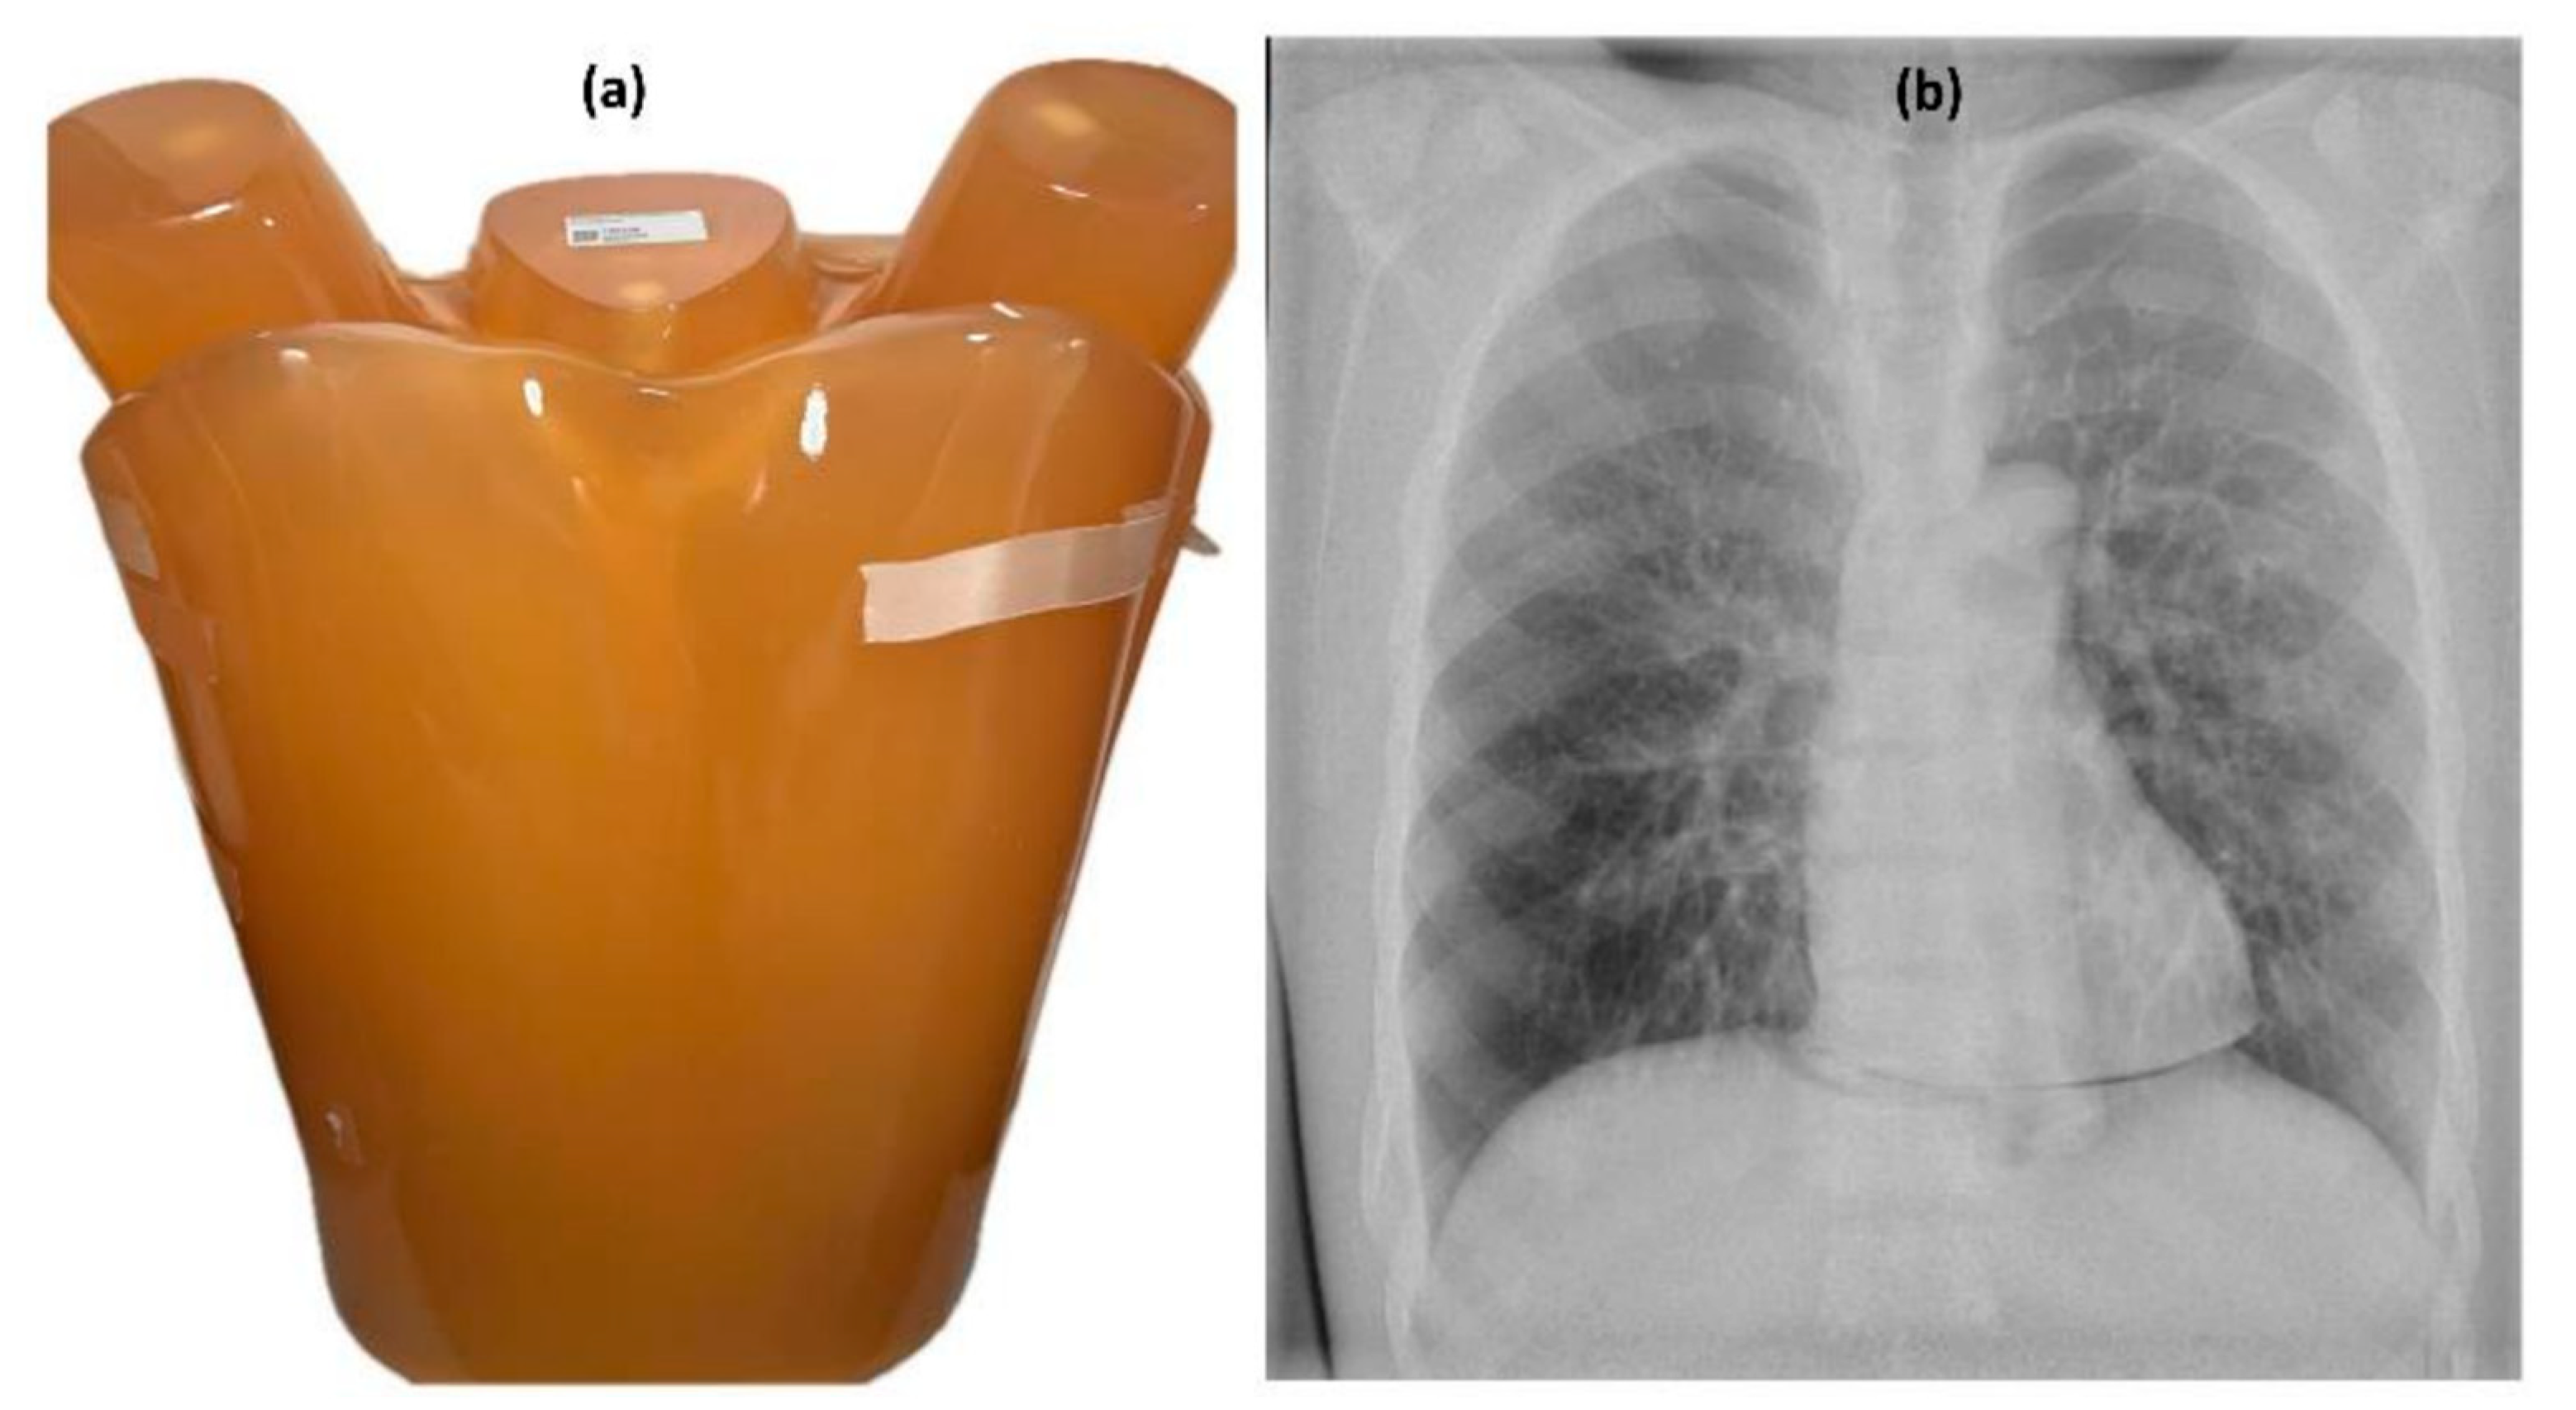

2.1. Protocol Settings and Image Acquisition